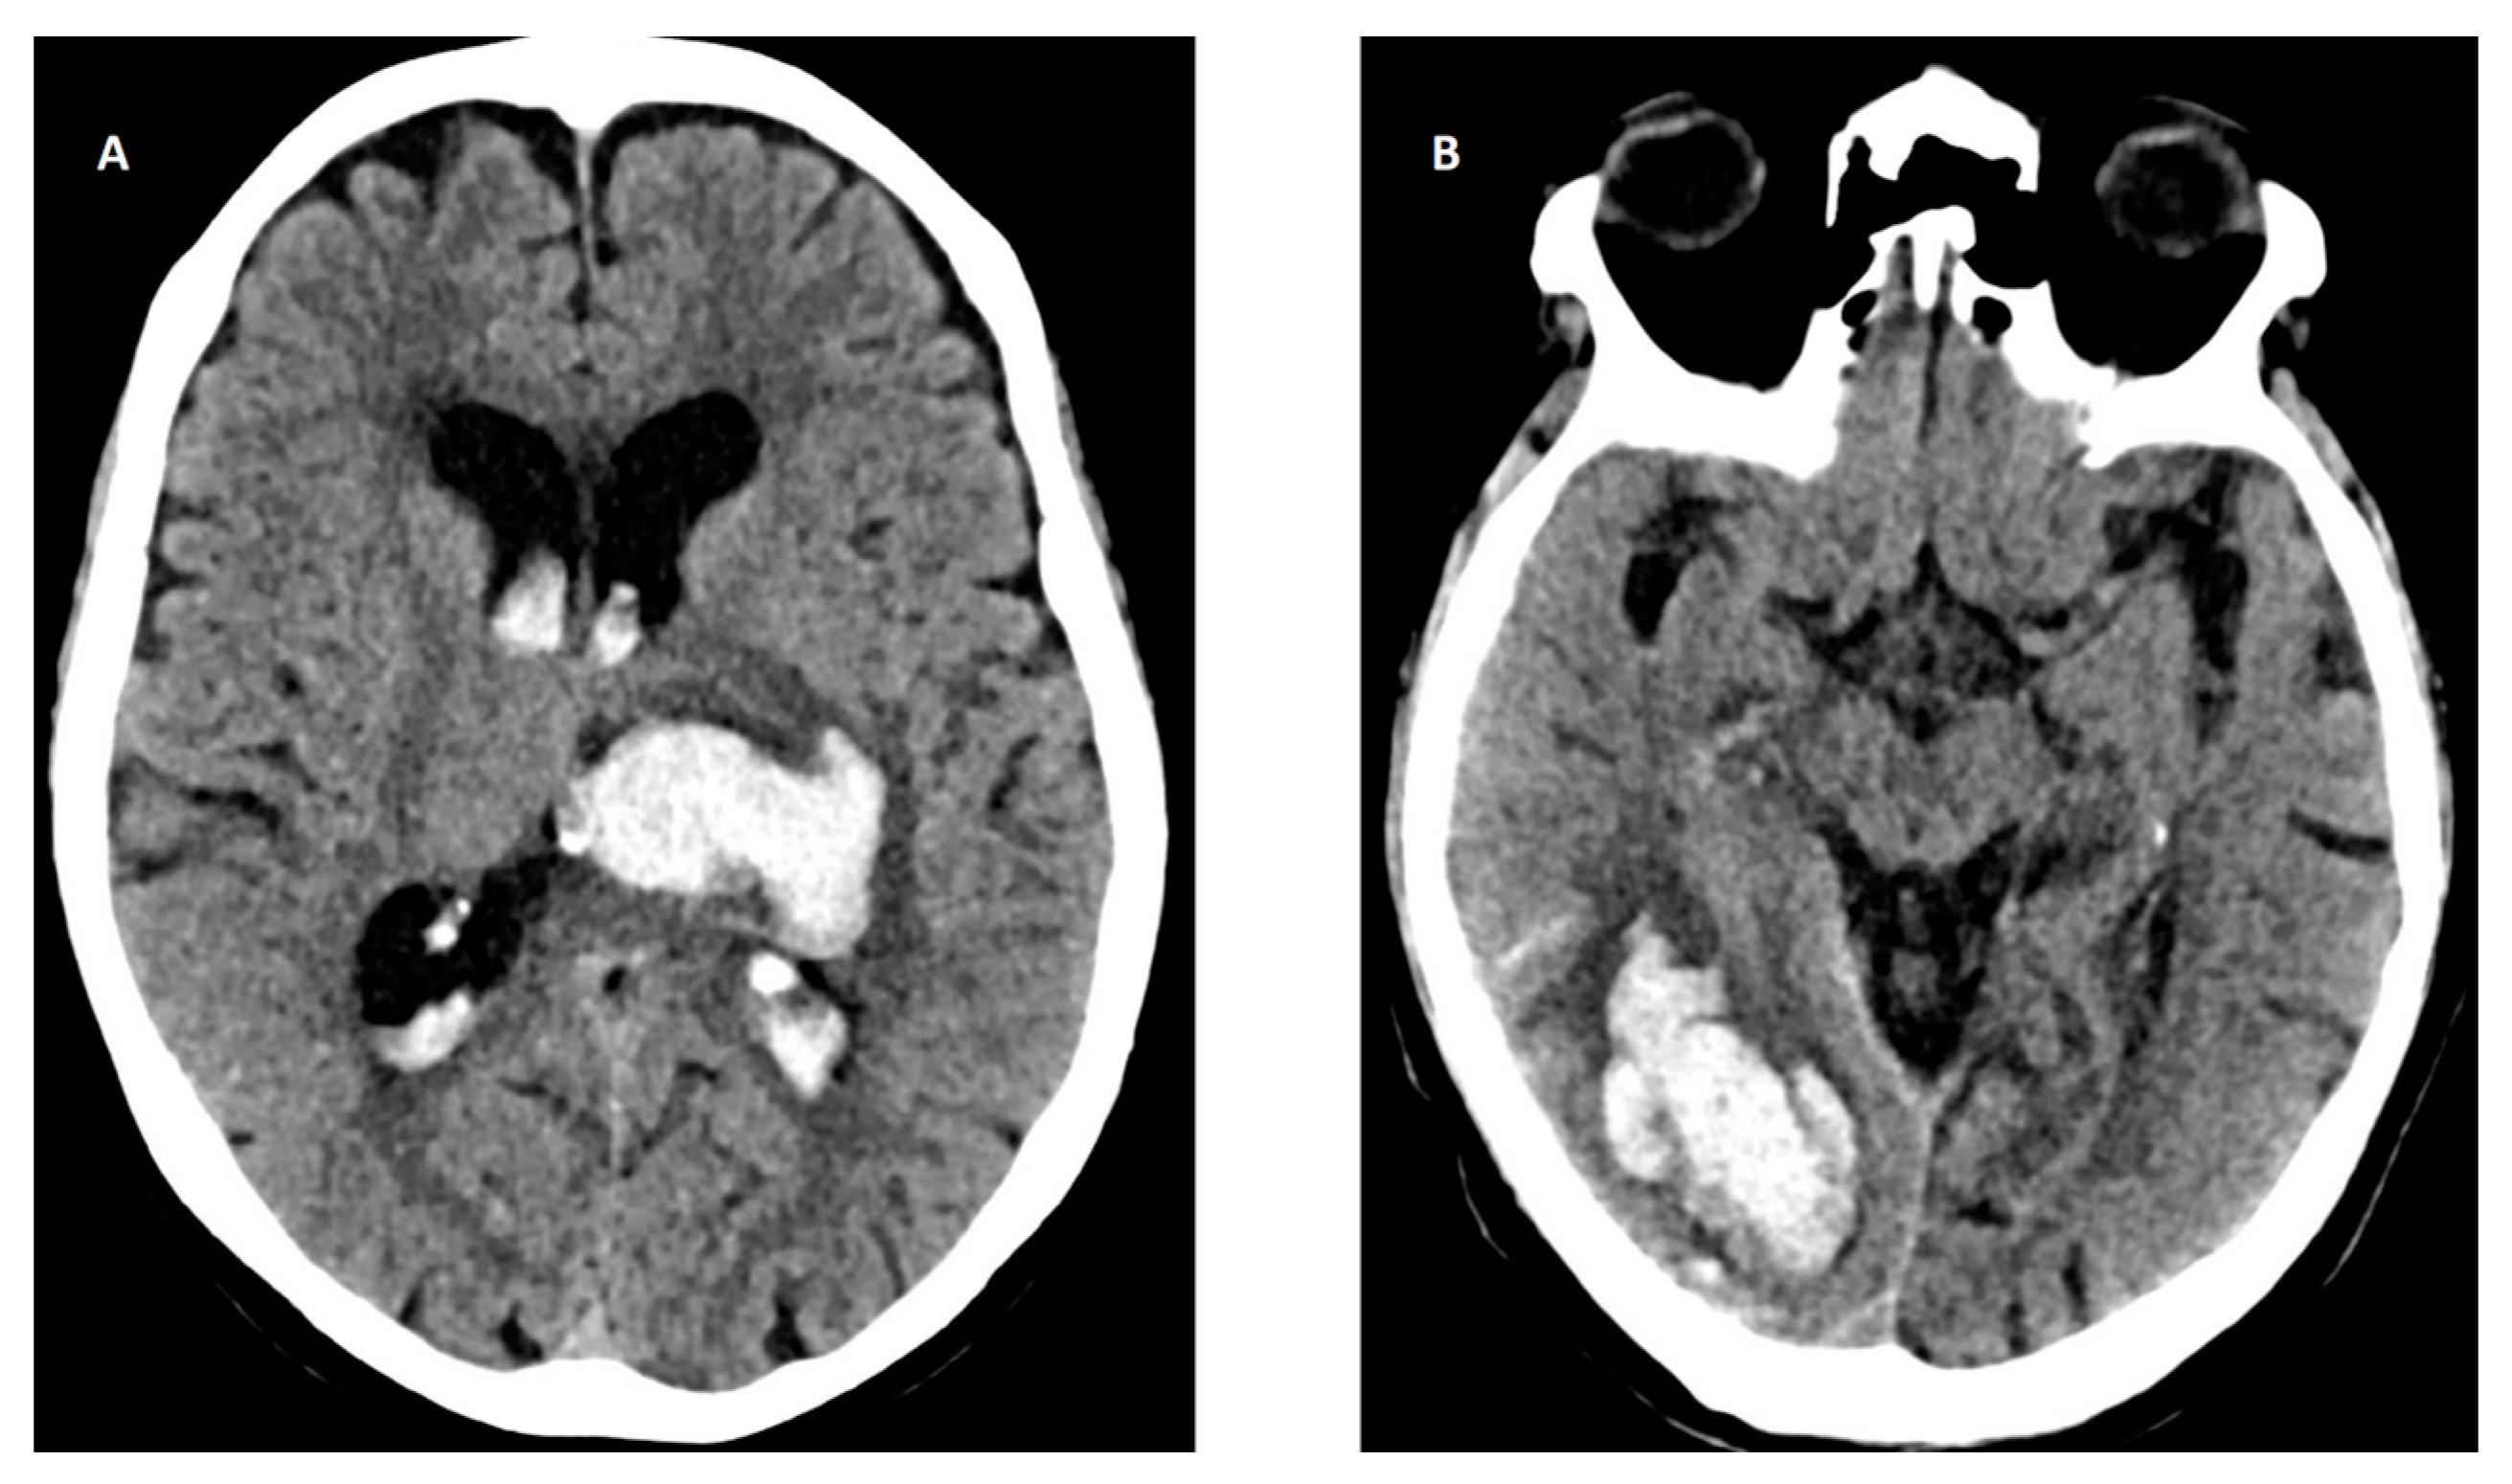

The most common cause of ICH is small vessel disease due to hypertension or cerebral amyloid angiopathy (CAA), a neurodegenerative age-dependent disorder characterized by amyloid deposition in the small cortical and leptomeningeal arteries, with an increased risk of IS and ICH [112]. Other causes include hemorrhage due to sinus thrombosis, rupture of vascular malformations (i.e., arteriovenous malformations, cavernous angiomas, and cerebral aneurysms), or neoplasms [113]. The location of ICH is associated with its etiology. In spontaneous (non-traumatic) ICH, lobar hematoma location may be indicative of underlying CAA, whereas non-lobar hemorrhages (basal ganglia, thalamus, and pontine) are almost always caused by hypertensive arteriopathy (Figure 4).

Figure 4.

Head CT of intracerebral hemorrhage (ICH). (A) Deep basal ganglia ICH in the left hemisphere with intraventricular hemorrhage (IVH) due to hypertension. (B) Lobar ICH in right occipital lobe with subarachnoid hemorrhage (SAH) probably due to cerebral amyloid angiopathy (CAA).